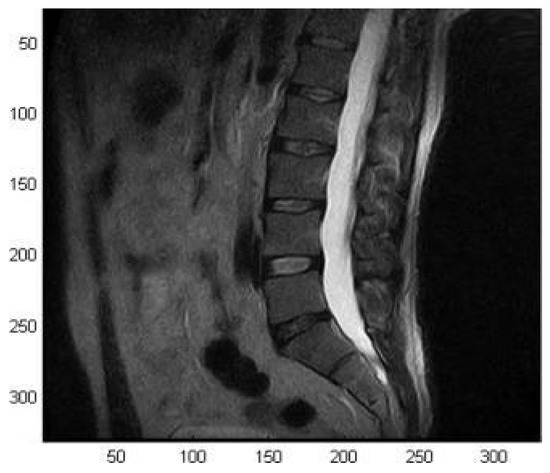

Experimental results performed on the two-element volume coil for spinal column imaging with an open 0.5 T scanner (MROpen, Paramed srl, Genova, Italy) confirmed the full-wave simulation results in terms of elements decoupling and magnetic field pattern (Figure 6).

In particular, the presence of the shielding system did not significantly alter the decoupling between coil elements but determined a magnetic field intensity decrease while still preserving the homogeneity. Finally, the coil was used for the acquisitions of a volunteer’s spine (male, 45 years old, height: 185 cm, weight: 90 kg) with a spin-echo sequence (TE = 120 ms, TR = 3175 ms, FOV 30 × 30 cm2, matrix 256 × 192, slice thickness 4 mm, echo number 1, spacing between slices 5 mm, number of averages 1), showing its potential for providing high-quality images (Figure 7).

Figure 7. MR image of the spinal column of a volunteer (sagittal view) acquired with the spine volume coil. Reprinted from [42].